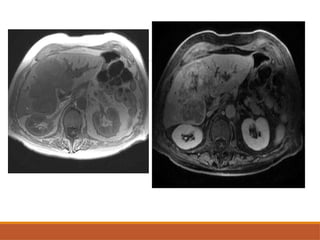

• #13 Axail T1 and T2 weighted images showing T1 hypointense and T2 hyperintense tumour in segment 6 of right lobe suggestive of giant hemangioma

MRI

T1WI: Hypo-intense relative to liver parenchyma.

T2WI: Significantly hyperintense –producing light bulb

appearance.

T1C+(GD):Nodular enhancement